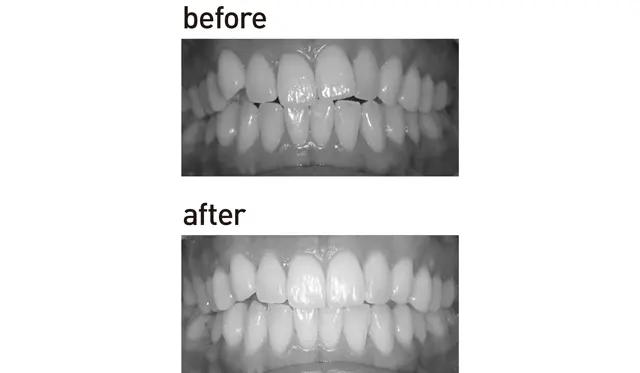

ワイヤー矯正

費用を抑えながらとにかく早く治したい人に

歯の表面にブラケットを装着しワイヤーを通して歯列を整える“王道”の矯正も歯茎の状態がよければ、50代からでも十分可能。最新式はブラケットもワイヤーも透明で目立ちにくい。取りはずしできないぶん、歯が早く動くので時間が短く費用も抑えられる。目安は部分矯正で¥220,000〜。